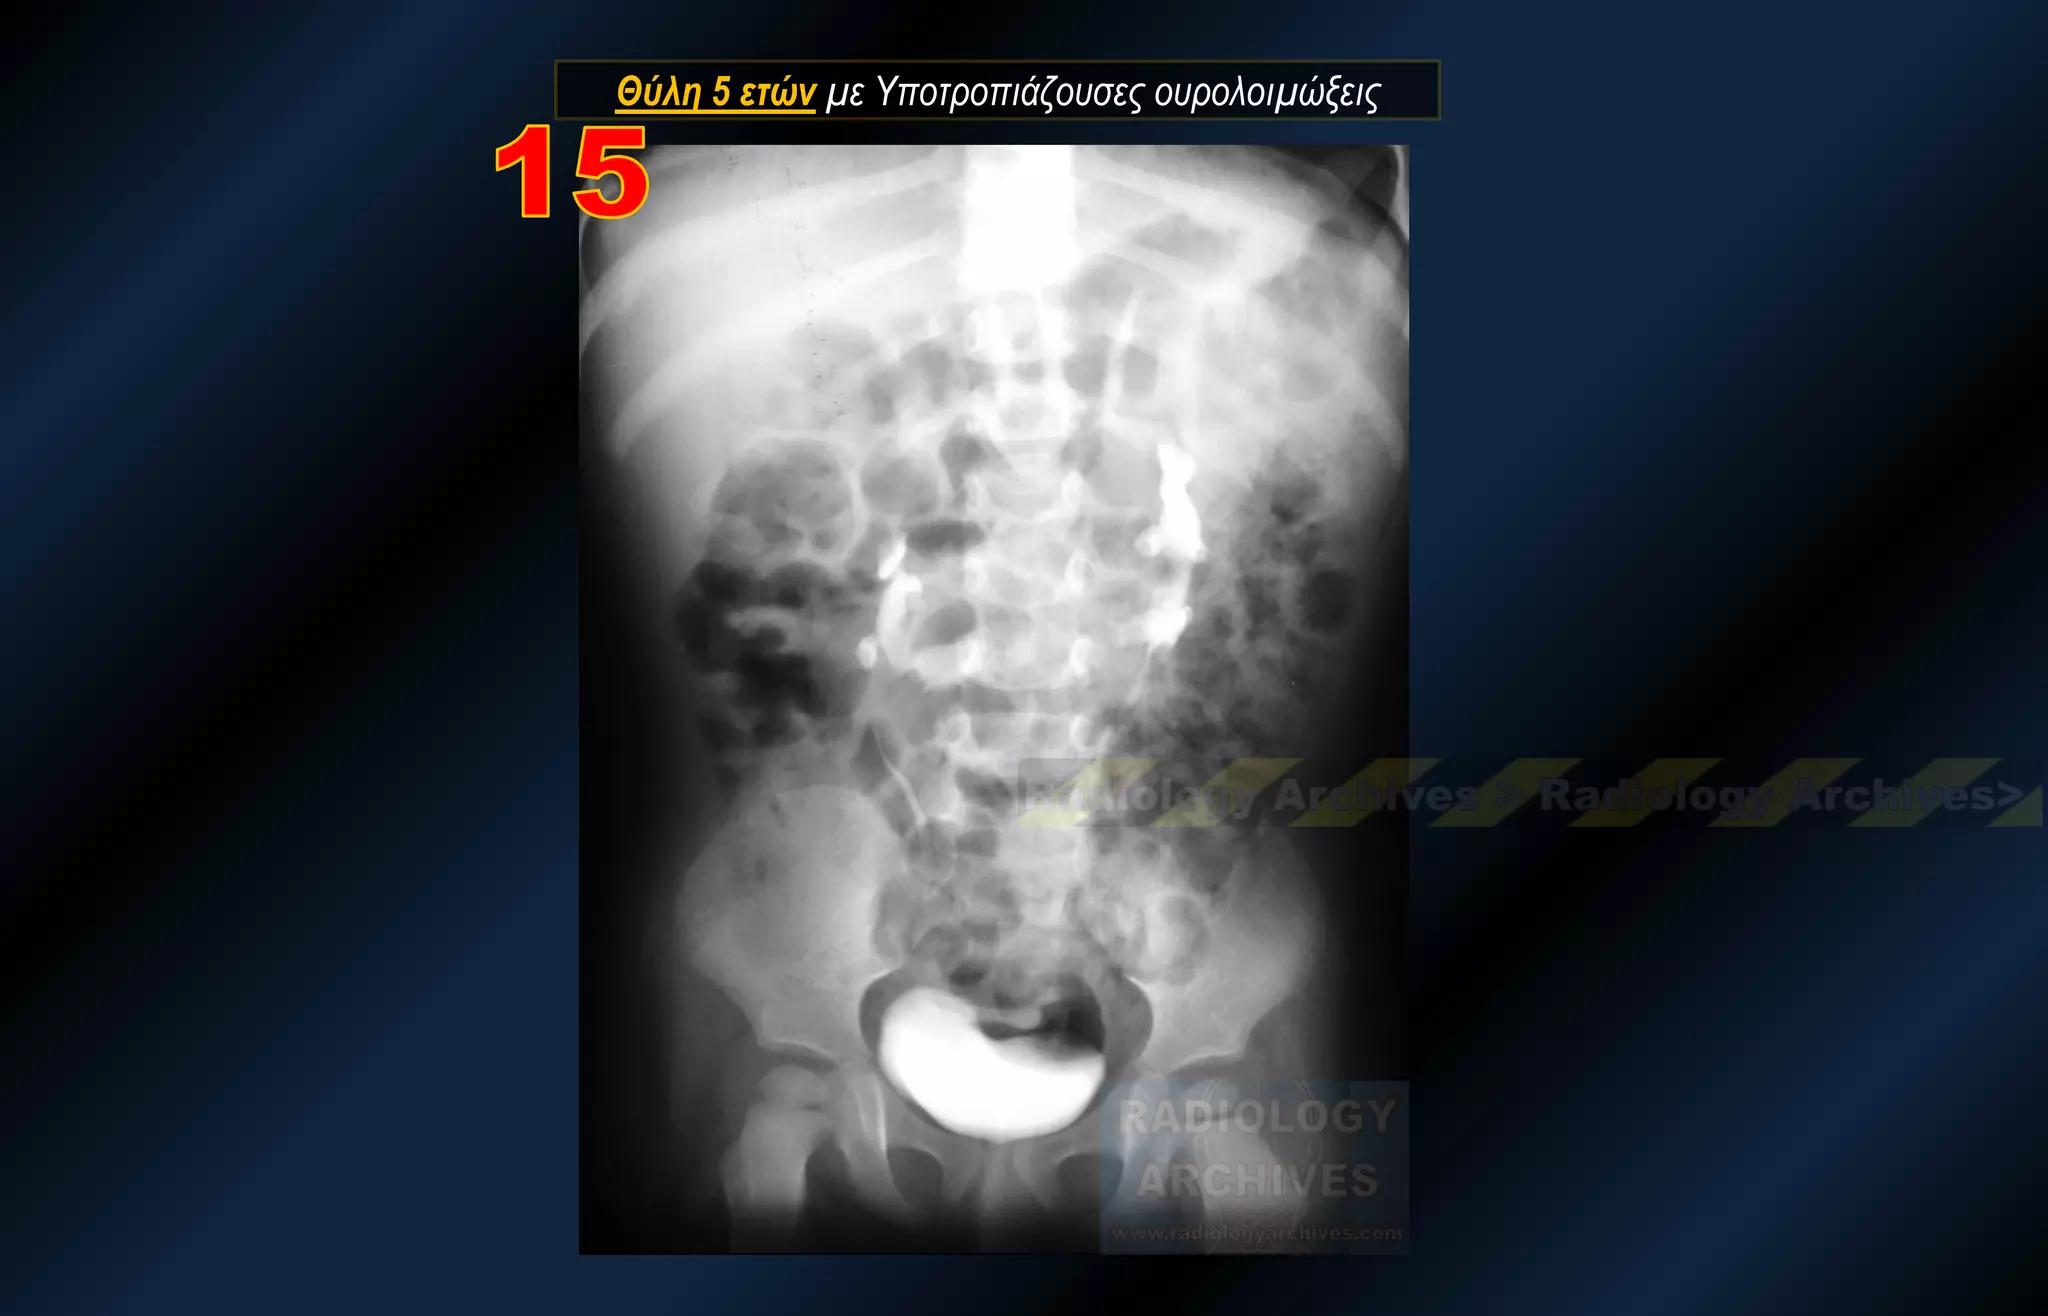

Θύλη 5 ετών με Υποτροπιάζουσες ουρολοιμώξεις

Θύλη 5 ετώνμε Υποτροπιάζουσες ουρολοιμώξεις